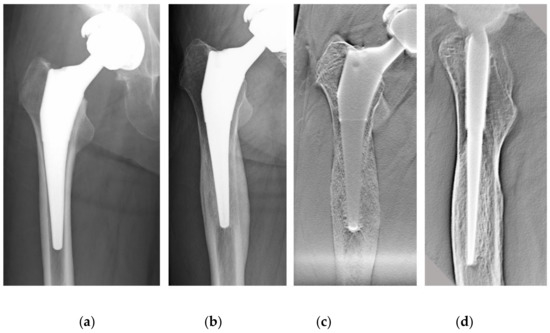

In all cases, bone formation was observed uniformly around the stem from proximal to distal (Figure 4).

Figure 4.

An 81-year-old female patient 3 y after THA. (a) Plain radiographs (lateral view); there was bone formation surrounding the stem (black arrowheads). (b) DTS (lateral view); in the same patient as in (a), bone formation was observed uniformly around the stem from proximal to distal (black arrowheads), and the stem–bone interface is seen more clearly in (b) than in (a). THA, total hip arthroplasty; DTS, digital tomosynthesis.

In the AP view, the thicknesses of the osteogenic layer were 0.54 ± 0.19 and 0.91 ± 0.31 mm in the 1 y group and 3 y group (p < 0.001), respectively, and there was a significant difference. In the lateral view, the thicknesses of the osteogenic layer were 0.69 ± 0.20 and 1.16 ± 0.27 mm in the 1 y group and 3 y group (p < 0.001), respectively, and this was also significantly different (Figure 5). No RLs with osteopetrosis in either group were noted.

Unlike the single tomogram obtained by general imaging with film, DTS acquires an arbitrary tomographic image in a single scan, reduces metal artifacts, and reconstructs the tomographic image using various algorithms [3,23,24]. In this study, we confirmed the osteogenic response around the stem using DTS. This is a layer of bone formation that occurs uniformly from proximal to distal on the surface of the HA-coated stem, and this reaction was defined as the surrounding bone formation (SBF).